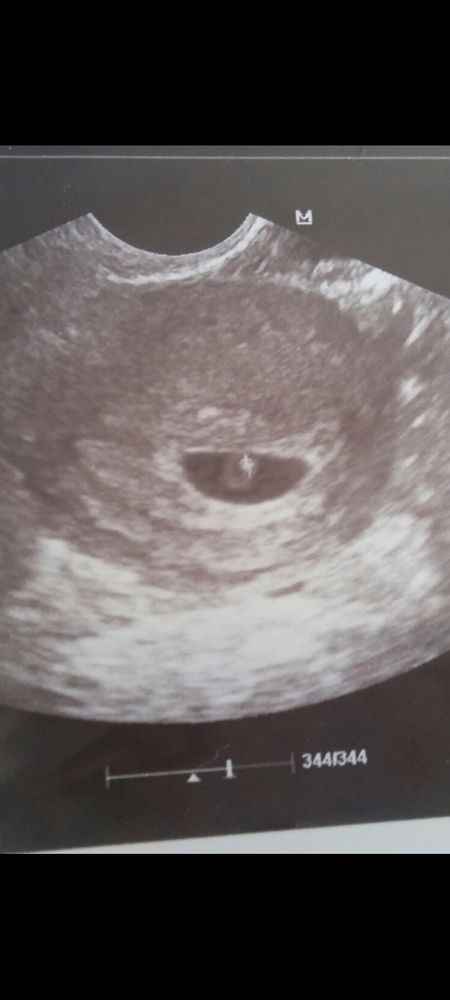

Всем приветик. Помогите понять,что это такое. Сегодня 26 ДЦ (мой цикл 36 дней) когда была овуляция не отслеживала. Две недели тянуло в правом боку. Сегодня сделала узи и врач сказал ,что у меня киста желтого тела. Но так же сказала ,что что-то видит на эндометрии, понять не могла ,сказала либо завтра или после завтра месячные придут ,либо это то о чем мы все всегда мечтаем. Сказала если не придут месячные сдавать хгч. Пока подождать надо. Написала под вопросом киста эндометрий ,ну сказала ,что это не оно ,просто нужно подождать. Может вы что то видите на снимке другое или может у кого-то такое было

Оленька, у меня была вот такая точка

Алена Алана, надейтесь на лучшее , я думаю у вас все получится. Тем более я не вижу у вас кисты , киста это когда 30 мм вот это уже киста. А у вас нормальное желтое тело